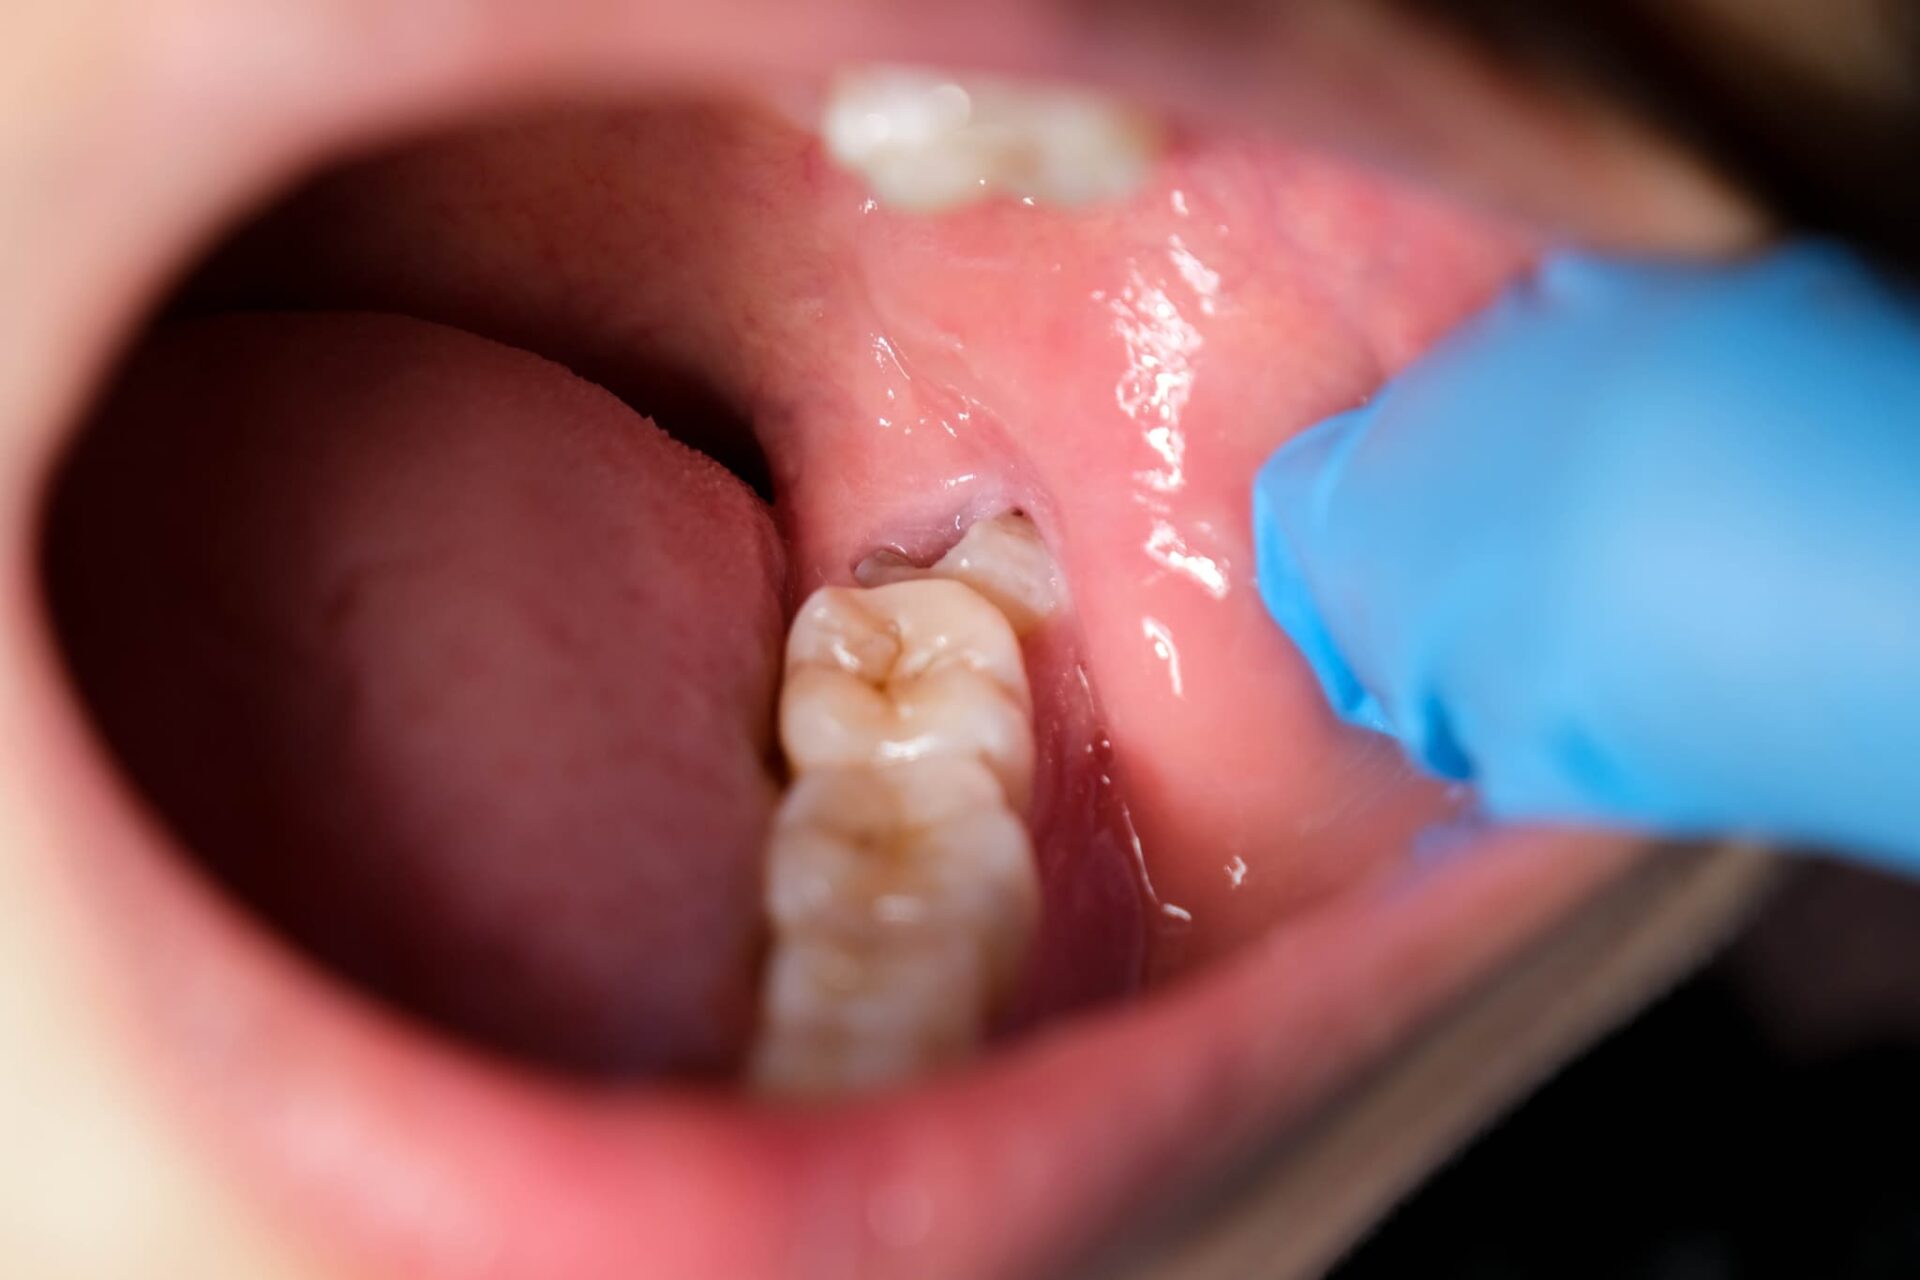

さらに、奥歯は見えにくいため、虫歯になっても自分で気づくのは難しいです。痛みなどの自覚症状が出るころには、虫歯が重症化していることも少なくありません。

奥歯はその名の通り、口の奥に位置しているため、歯ブラシが届きにくいです。また、食べ物を噛む面には複雑な構造の溝があるため、歯ブラシの毛先が届いていたとしてもしっかりと磨くのは難しく、磨き残しが生じやすいです。

奥歯は他の歯と比べて、生え方が不規則になることが多いです。特に、親知らずが生えてくると、隣接する第二大臼歯が傾いたり噛み合わせが悪くなったりすることがあります。噛み合わせが適切でないと食べ物が挟まりやすくなり、虫歯のリスクが高まります。